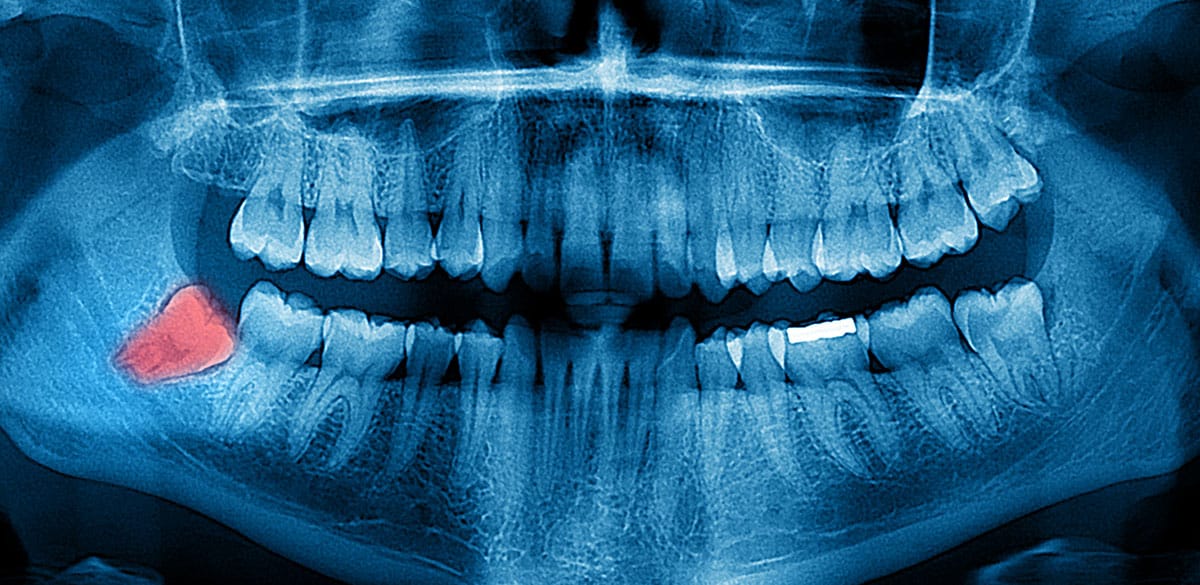

שן כלואה היא שן שאיננה מצליחה לבקוע מבעד לחניכיים, באופן מלא או חלקי, בעת הצמיחה שלה. הסיבות לתופעה זו הן מגוונות ובחלקן נעוצות בשינויים התזונתיים שעבר המין האנושי מאז ימי המהפכה התעשייתית. מכל מקום, שן בינה שאין לה מספיק מקום בלסת, או שצומחת על צידה או שממוקמת בצורה לא נכונה בלסת, לא תצליח לחדור מבעד לרקמת החניכיים ותוגדר ככלואה.

ראשית, על מנת לקבוע באופן ודאי אם אכן מדובר בשן כלואה, יבצע רופא השיניים צילום רנטגן אשר יצביע על מצבה של שן הבינה. כאשר יתברר כי שן הבינה אכן כלואה, במלואה או באופן חלקי, והיא גורמת לבעיות שצוינו קודם לכן, במרבית המקרים ימליץ הרופא על עקירה או על קטימת השן. שן בינה כלואה שאיננה גורמת לכאב ואיננה משפיעה לרעה על השיניים הסמוכות לה, לא תדרוש טיפול אלא מעקב שגרתי.

שיני הבינה התחתונות, לעומת זאת, ממוקמות בסמיכות לעצב המנדיבולרי, אשר מעביר את התחושה לשפה התחתונה, ולעצב הלינגואלי, אשר מעביר את התחושה ללשון. לכן, קיים סיכון לפגיעה עצבית בעת עקירה של שן בינה תחתונה. כאשר יוחלט על עקירה של השן הכלואה התחתונה, יעריך הרופא את מידת המורכבות של ההליך באמצעות צילומי רטנגן ו-CT, שיבהירו אם ניתן לבצע עקירה בהליך פשוט או אם נדרשת התערבות של מומחה.